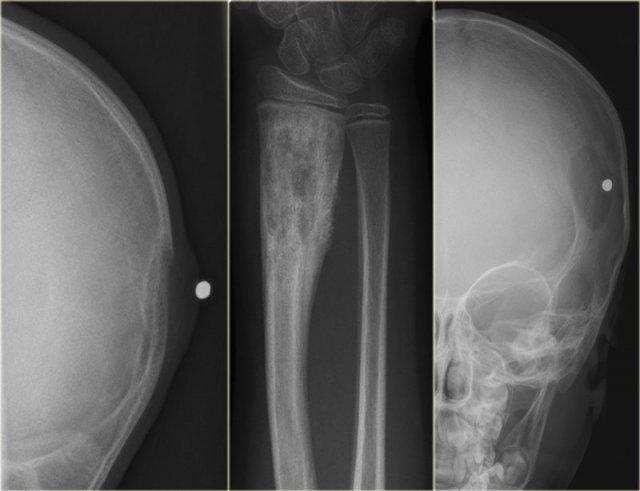

- trái

Tổn thương tiêu xương xuất phát từ hộp sọ thần kinh kèm theo sưng phần mềm liên quan. - giữa

Tổn thương hỗn hợp tiêu xương-xơ cứng, không rõ ranh giới với phản ứng màng xương đặc. - phải

Tổn thương tiêu xương sọ được xác định rõ ràng. Không có dấu hiệu ‘mảnh xương chết dạng nút’, vốn ít nhiều mang tính đặc trưng bệnh lý.